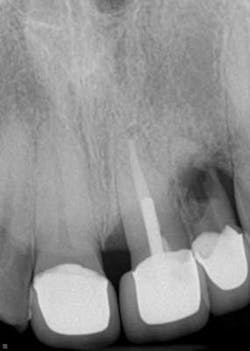

A healthy 36-year-old male presents to the office with a chief complaint of a loose front tooth. A radiograph revealed significant bone loss around tooth No. 10 in addition to the focalized loss of internal tooth structure in the apical one-third of the root. Obvious perforation of the root was observed. Clinical exam revealed a lack of recession, probing depths of 8+ mm with a Class III mobility. No drainage point or fistula were noted. The patient indicated that he had the crowns placed in the anterior area eight years ago and has not had any complications since then. He furthermore admits to lack frequent dental visits during this time.

Differential diagnoses of internal and external resorption were given. Earlier radiographs would definitely aid in a more accurate and definitive diagnosis, but ultimately, internal resorption was given due to the focal point of radiolucency within the pulp chamber area. While there could be debate on this, the ultimate fate of the tooth did not change. Due to the extent of the defect (perforation through external root surface) and the advanced bone loss and periodontal disease, it was recommended that that tooth be removed and other restorative options be assessed. Upon removal of the tooth, there was very little root structure left as it came out in a multitude of pieces.